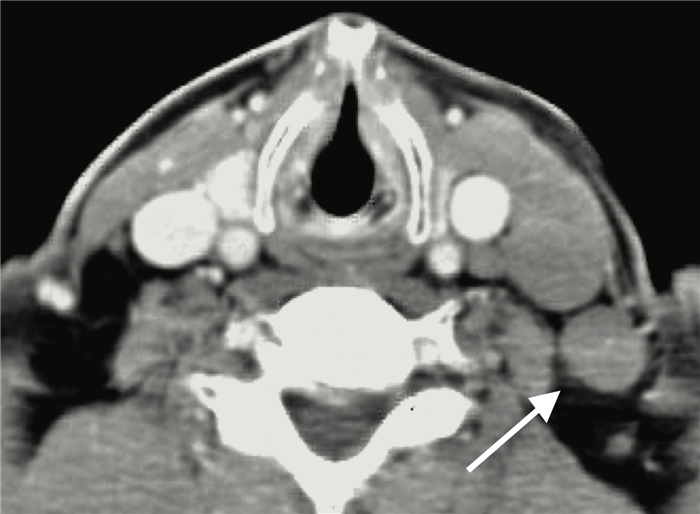

На ниже представленном постконтрастном КТ изображении визуализируется увеличение и контрастное усиление лимфатических узлов III группы.

На постконтрастном изображении белой стрелкой указан увеличенный лимфатический узел IV группы. У пациента удалена правая доля щитовидной железы и правая яремная вена, что указано чёрной стрелкой, всвязи с папиллярной карциномой.

На постконтрастном изображении белой стрелкой указан увеличенный лимфатический узел V группы.

На постконтрастном изображении белой стрелкой указан увеличенный лимфатический узел VI группы.